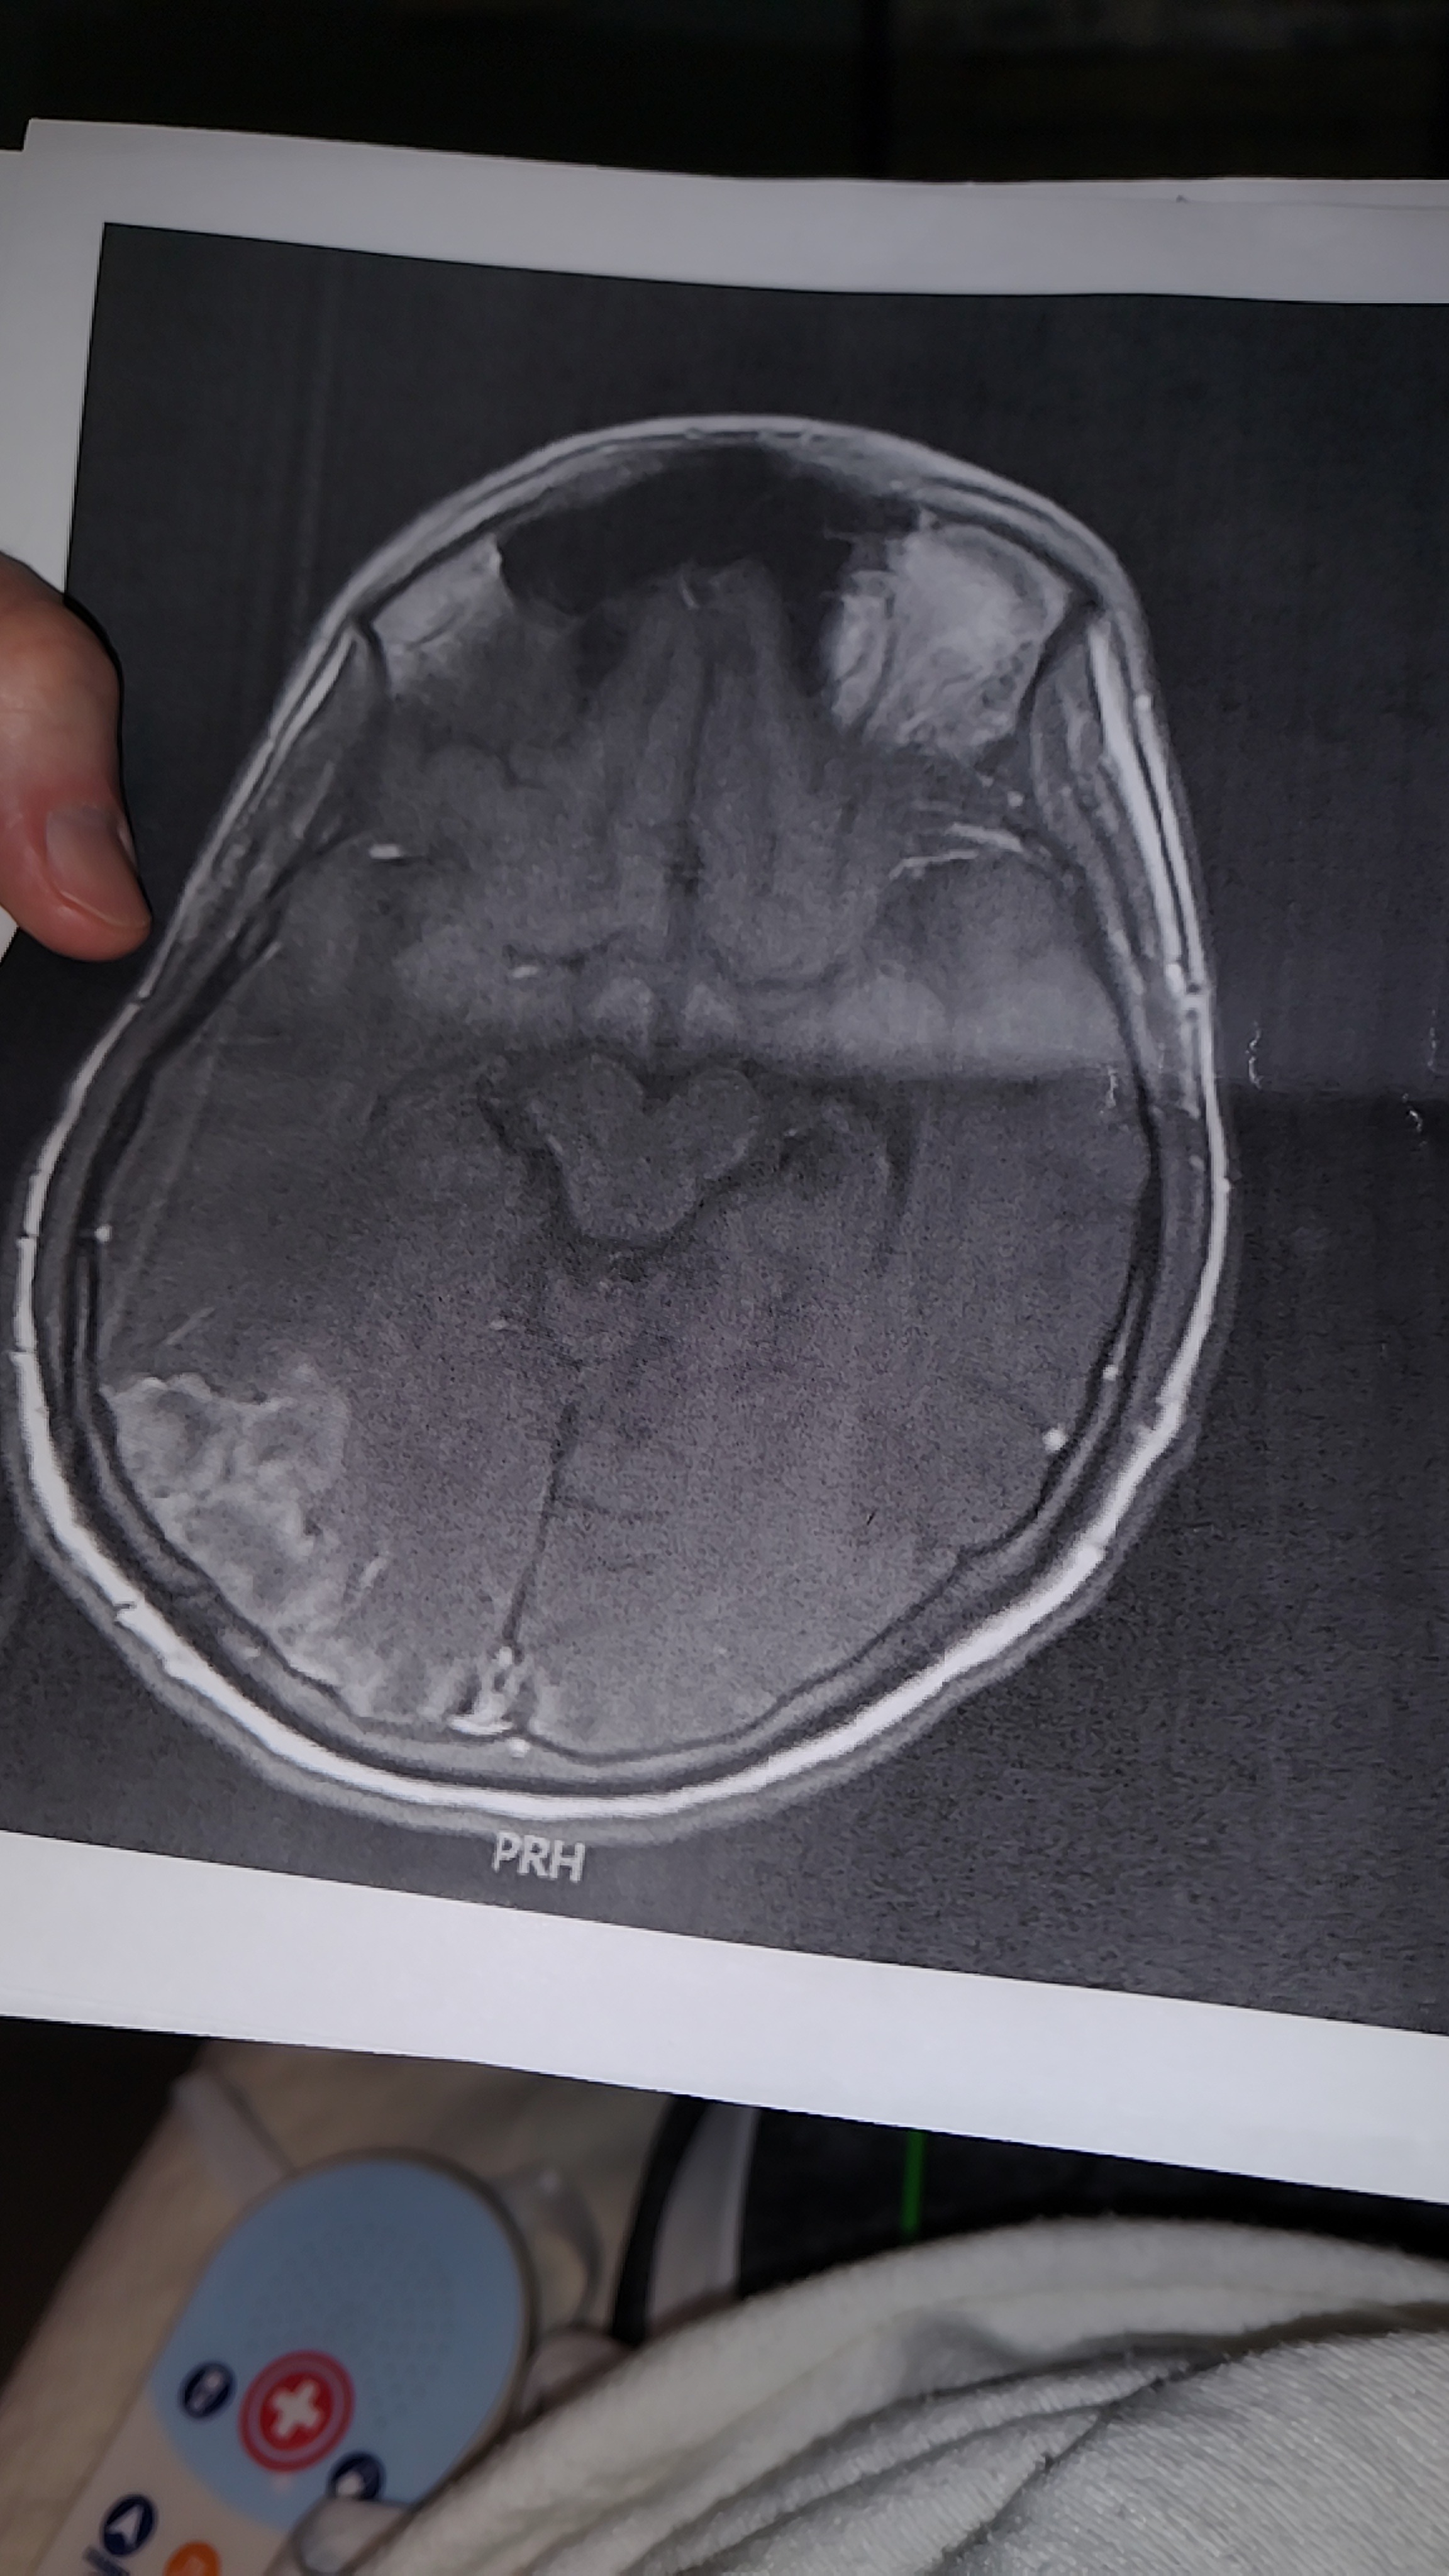

Hello, my name is Jose. I'm 22 years old. A year ago, I arrived to Nashville, TN, thinking just to help my mother who is in Colombia. Two months ago, I started feeling sick, and when I arrived at the clinic, the doctors rushed me to the hospital. The next day, they confirmed I had cancer in one of my testicles. I underwent surgery to remove the testicle. However, days later, several tests confirmed that the cancer had already spread to my lungs, liver, and brain. I want to ask for your help, please, since I have no one else in this country. My health is delicate, and I cannot travel to Colombia. The Government denied to my My mother a humanitarian visa to take care of myself, so now I’m alone. I was hospitalized for a month, already received five radiation therapies, and still need several chemotherapy treatments. The doctor believes I need at least 12 more chemotherapy treatments, and I will be unable to work for more than six months. I have to pay the hospital bill, my monthly rent, and my monthly expenses. Whatever you want to help me with, believe me, it will mean a lot to me.